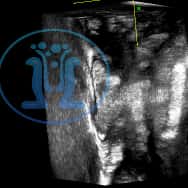

Ενα συριγγιο πρωκτού σε 45 χρονών ασθενή με πολλαπλά δερματικά στόμια δεξιά και αριστερά. Το πρωκτικό στόμιο είναι στην 6η ώρα σε εν τω βαθει επίπεδο, σε απόσταση 21 mm από την είσοδο του δακτυλίου.

Τα στόμια επικοινωνούν μεταξύ των και παρουσιάζουν εκροή υγρού. Η όλη κατάσταση εμφανίσθηκε μετά από παροχέτευση εκτεταμένου περιεδρικού αποστήματος που έδωσε την εντύπωση γάγγραινας Fournier. Η κλινική και υπερηχοτομογραφικη εικόνα ειναι χαρακτηριστική πεταλοειδούς συριγγίου.